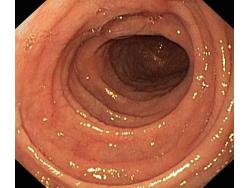

Celiakia